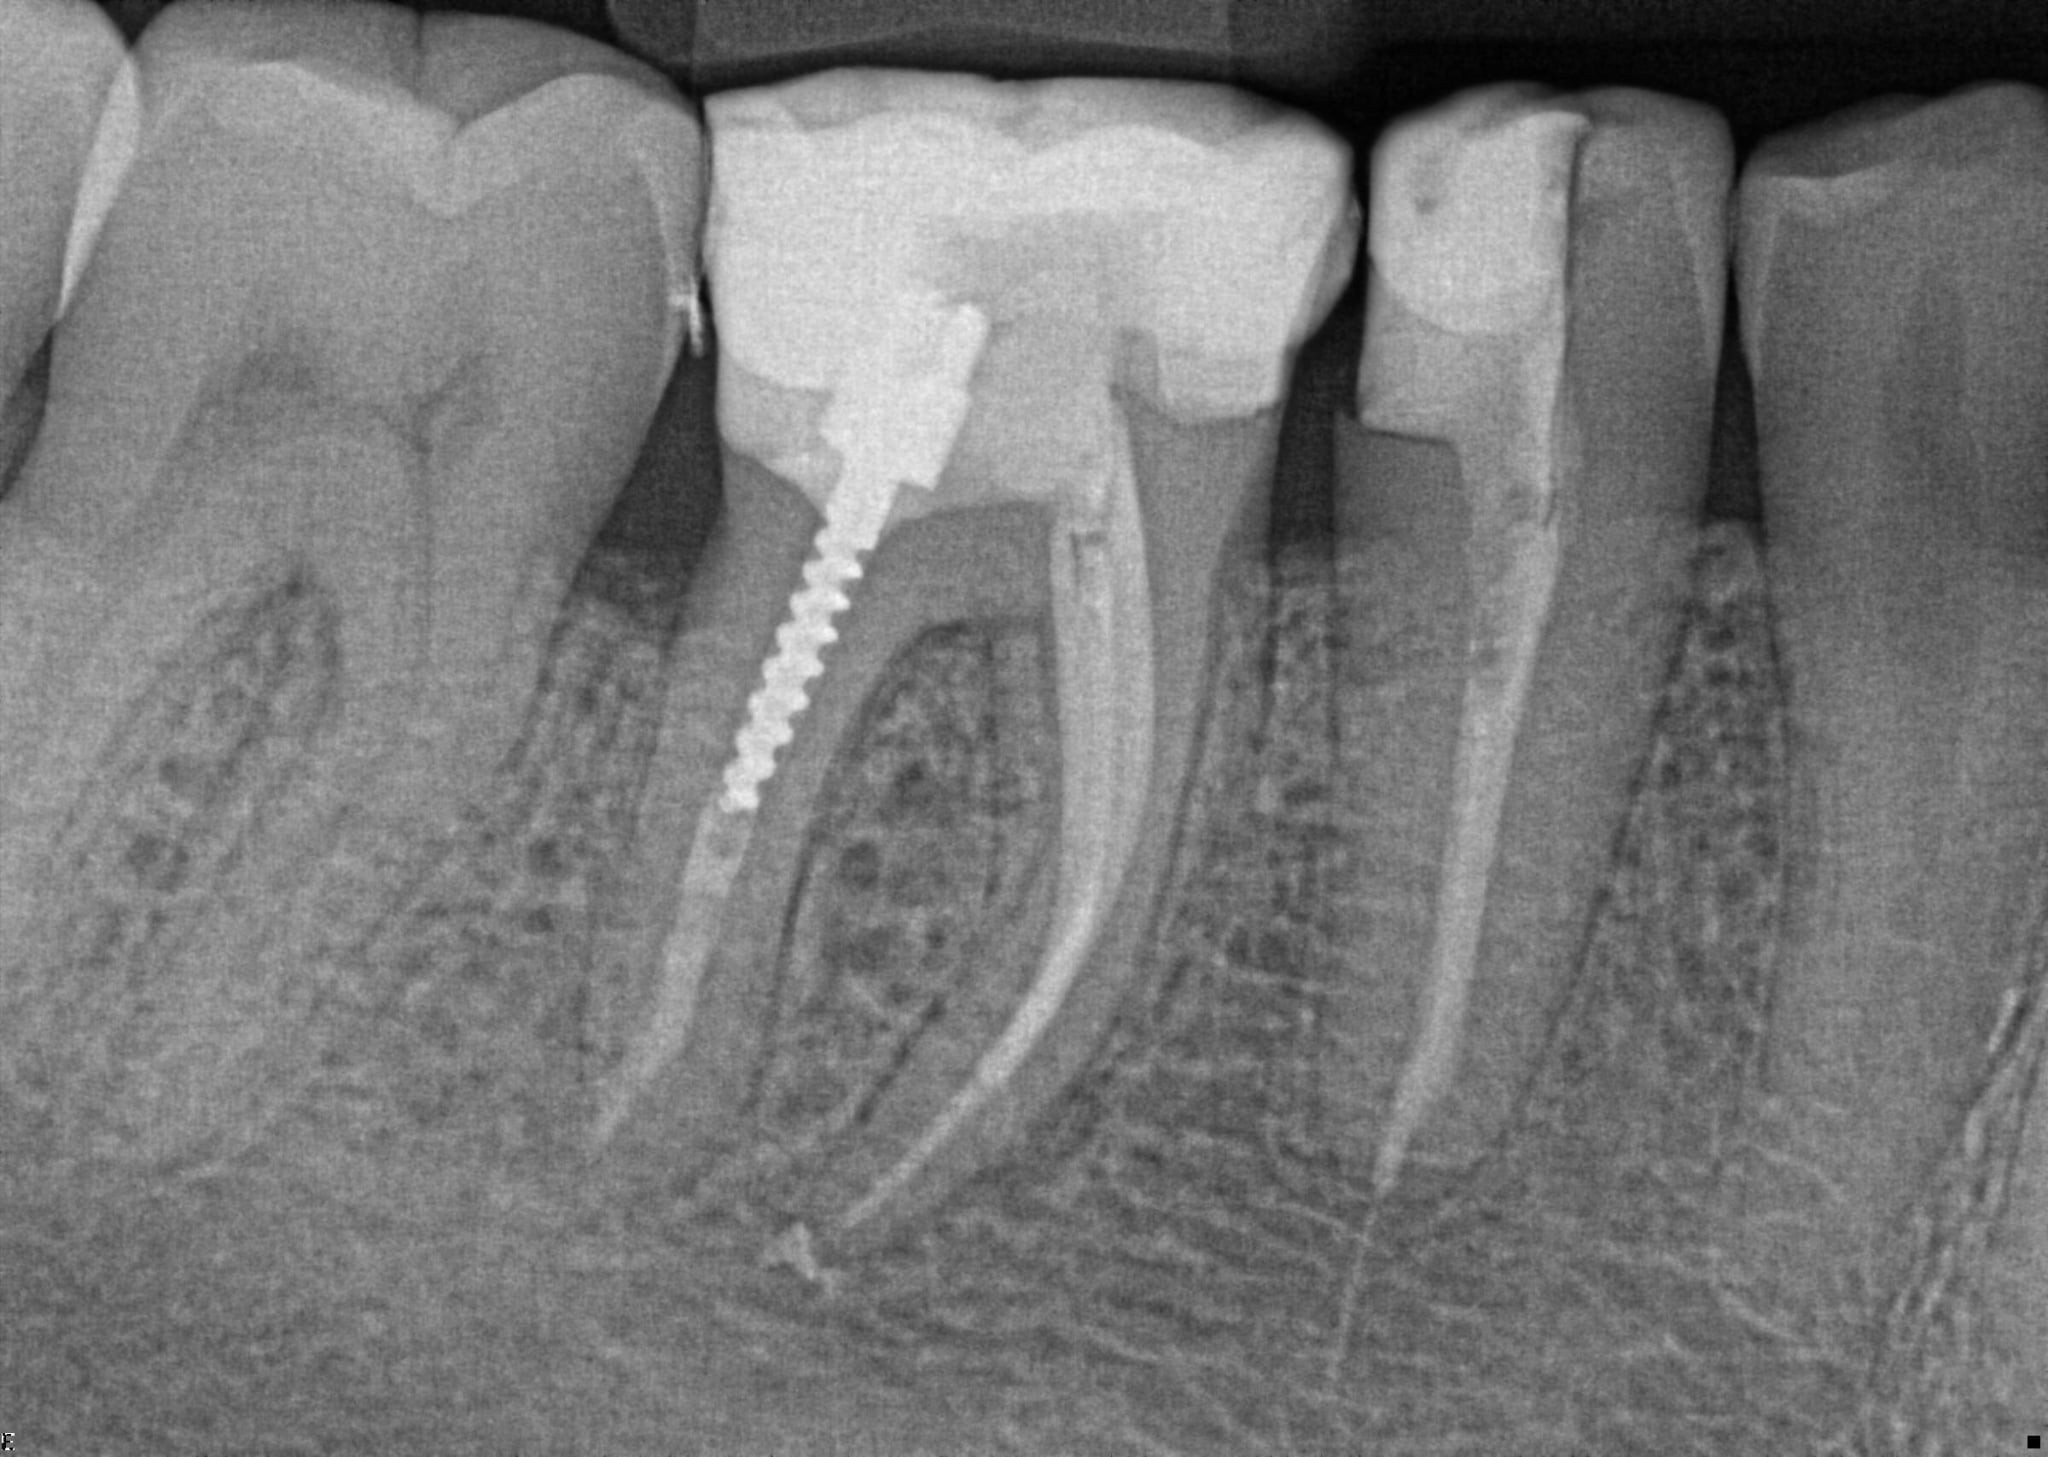

2. What option can describe the post placement in the X ray bellow for the tooth # 4.6?